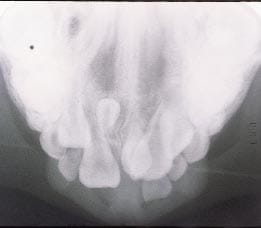

Phim toàn cảnh bệnh nhân đa răng dư

Răng dư có thể xảy ra một hoặc nhiều răng, một phía hoặc hai phía, đã nhú ra hoặc còn ở mọc ngầm và ở một hoặc cả hai hàm. Đa răng dư là hiếm gặp ở cá nhân không có các bệnh lý hoặc hội chứng liên quan. Những điều kiện thường gặp có liên quan với một tỷ lệ lớn của răng dư bao gồm hở môi và vòm miệng, loạn sản cleidocranial* (Hình 3), và hội chứng Gardner. Răng dư liên quan đến kết quả hở môi và vòm miệng từ phân chia của ngà răng trong quá trình hình thành hàm ếch. Tần số xuất hiện răng dư ở bộ răng vĩnh viễn trong khu vực hàm ếch ở trẻ em hở môi hoặc vòm miệng riêng lẻ hoặc cả hai đã được thống kê là 22,2%. Tần số xuất hiện răng dư ở những bệnh nhân bị loạn sản cleidocranial dao động từ 22% ở khu vực răng cửa hàm trên đến 5% ở khu vực răng hàm. Mặc dù giới tính không quan trọng trong phân bổ răng dư ở bộ răng sữa, nhưng ở bộ răng vĩnh viễn, nam giới bị ảnh hưởng gấp hai lần so với ở phụ nữ.